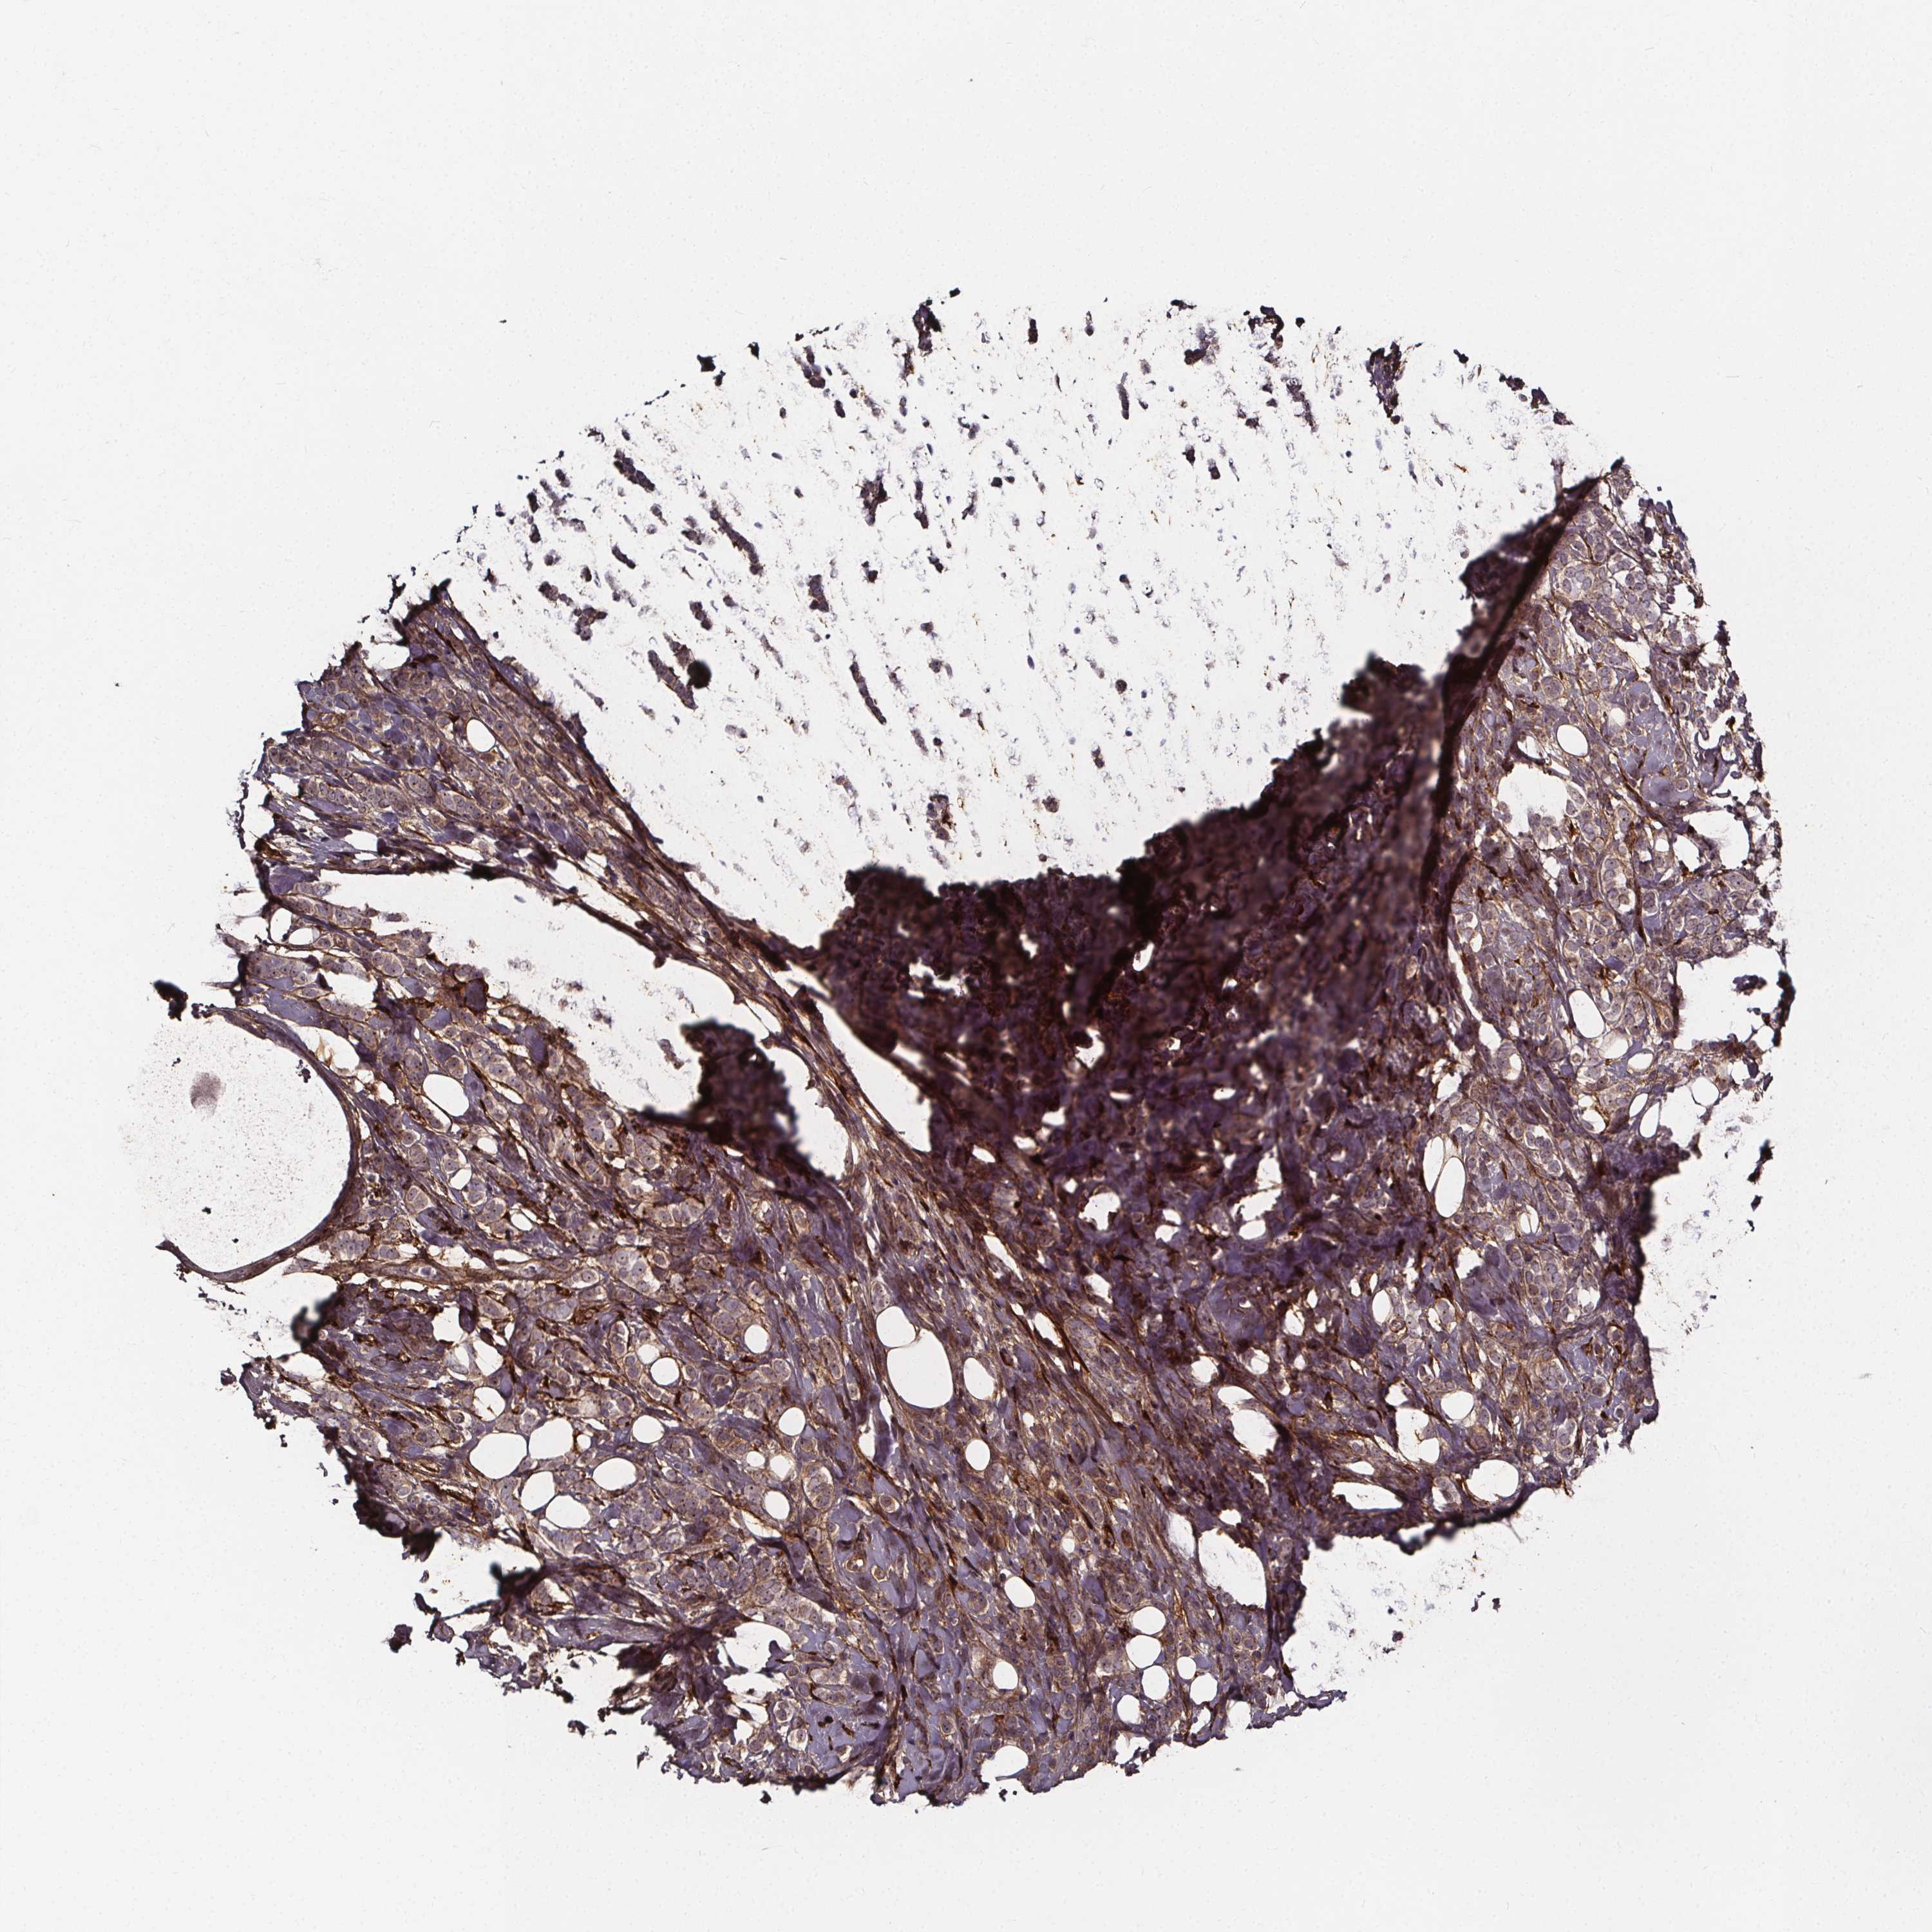

CANCER BREAST CANCER Show tissue menu

BRCA TCGA BRCA VALIDATION PROTEIN EXPRESSION